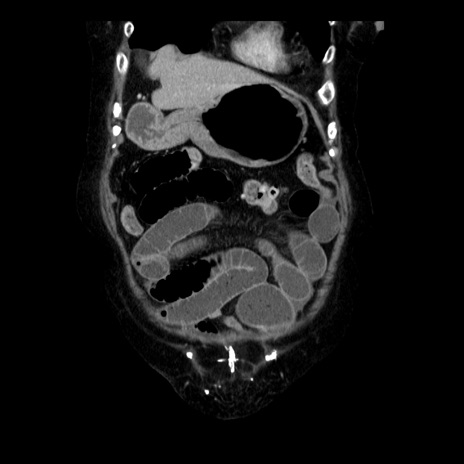

症例14(冠状断像)

【症例】 90歳代女性

【主訴】 腹痛・嘔吐

【現病歴】今朝から左側腹部痛を認めた。 経過観察していたが、嘔吐を認めたため来院。

【既往歴】 子宮癌術後

【身体所見】 意識清明、BP 127/54mmHg、P 98bpm Sp02 95%(RA)、BT 35.8°C、腹部平坦・軟腸ぜん動音聴取良好、右下腹部圧痛(+) 反跳痛なし

【データ】WBC 9800、CRP 0.46